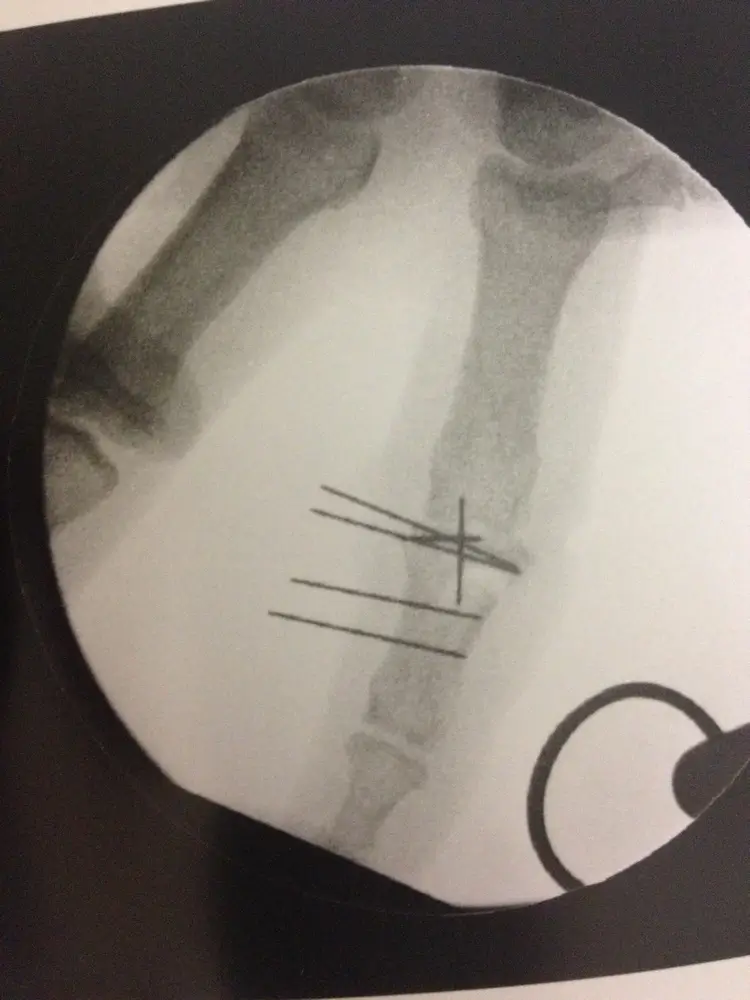

Dans le cadre des urgences de la main et du poignet, le chirurgien de la main Aude Le Corre est appelée pour la réalisation de soins ou pour des opérations chirurgicales pour des plaies, des infections, des brûlures, et de la traumatologie (fractures). Elle intervient aux urgences de la main depuis 2013.

Vous trouverez ci-dessous des exemples d'interventions SOS main :

- fractures